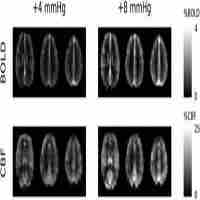

| Description | Journal: NeuroImage Calibrated fMRI techniques estimate task-induced changes in the cerebral metabolic rate of oxygen (CMRO2) based on simultaneous measurements of cerebral blood flow (CBF) and blood-oxygen-level-dependent (BOLD) signal changes evoked by stimulation. To determine the calibration factor M (corresponding to the maximum possible BOLD signal increase), BOLD signal and CBF are measured in response to a gas breathing challenge (usually CO2 or O2). Here we describe an ASL dual-acquisition sequence that combines a background-suppressed 3D-GRASE readout with 2D multi-slice EPI. The concatenation of these two imaging sequences allowed separate optimization of the acquisition for CBF and BOLD data. The dual-acquisition sequence was validated by comparison to an ASL sequence with a dual-echo EPI readout, using a visual fMRI paradigm. Results showed a 3-fold increase in temporal signal-to-noise ratio (tSNR) of the ASL time-series data while BOLD tSNR was similar to that obtained with the dual-echo sequence. The longer TR of the proposed dual-acquisition sequence, however, resulted in slightly lower T-scores (by 30%) in the BOLD activation maps. Further, the potential of the dual-acquisition sequence for M-mapping on the basis of a hypercapnia gas breathing challenge and for quantification of CMRO2 changes in response to a motor activation task was assessed. In five subjects, an average gray matter M-value of 8.71±1.03 and fractional changes of CMRO2 of 12.5±5% were found. The new sequence remedies the deficiencies of prior combined BOLD-ASL acquisition strategies by substantially enhancing perfusion tSNR, which is essential for accurate BOLD calibration. |